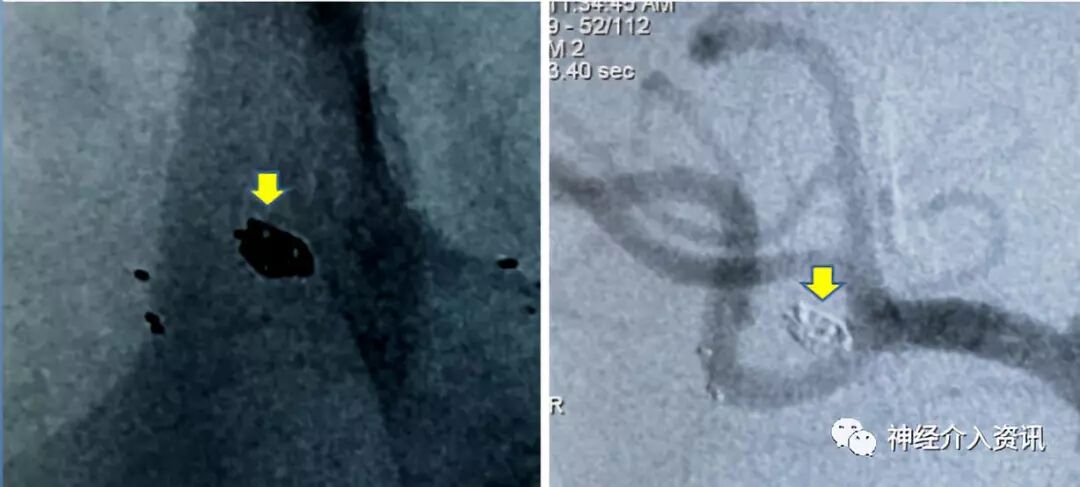

图三 大脑中动脉瘤致密栓塞

图四 黄箭头显示应用一枚Axium™ Prime ES 1mm*3cm弹簧圈将脉络膜前动脉动脉瘤致密栓塞,脉络膜前动脉保存良好(红箭头)

先处理大脑中动脉分叉部动脉瘤,应用Echelon-10微导管在微导丝导引下置于动脉瘤的中心,将支架导管置入同侧大脑中动脉M2中,释放4*15mm Solitaire™ AB支架一枚,跨越动脉瘤颈,应用Axium™ Prime ES 1.5mm*3cm弹簧圈及1mm*3cm弹簧圈将大脑中动脉动脉瘤致密填塞,在栓塞过程中微导管始终保持稳定,弹簧圈顺利推送无顶管现象,完成对该动脉瘤的栓塞;继续处理右脉络膜前动脉动脉瘤, Echelon 10在微导丝导引下置于动脉瘤的中心,释放3.5*15mm支架一枚,跨越动脉瘤颈,应用一枚Axium™ Prime ES 1mm*3cm弹簧圈将动脉瘤致密填塞,完成对两个动脉瘤的栓塞。

微小动脉瘤一旦微导管移位,在管内还有余圈时精准复位会非常困难,在本例1.2mm微小动脉瘤的栓塞术中,推送弹簧圈时无“踢管”现象,微导管非常稳定,超柔软的圈的稳定安全效应尽显。

3虽然柔软,但成篮能力卓越